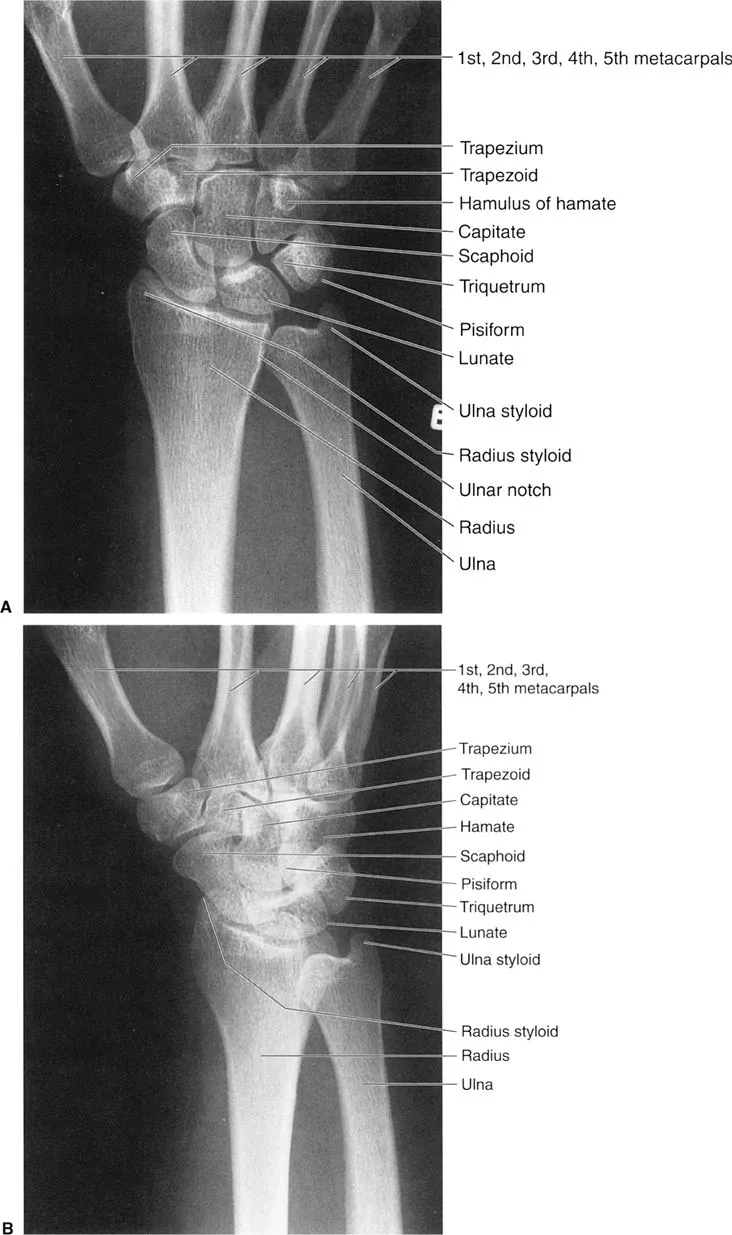

- X-ray: Initial for fractures, dislocations, arthritis (ABCS approach).

- CT: Complex fractures, bone tumors.

- MRI: Soft tissues (ligaments, menisci), marrow edema, AVN.

- Key pathologies: Osteoarthritis (osteophytes), RA (erosions), common fractures.